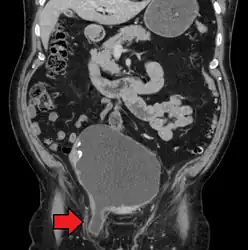

An incarcerated inguinal hernia as seen on cross sectional CT scan -

A frontal view of an incarcerated inguinal hernia (on the patient's left side) with dilated loops of bowel above. -